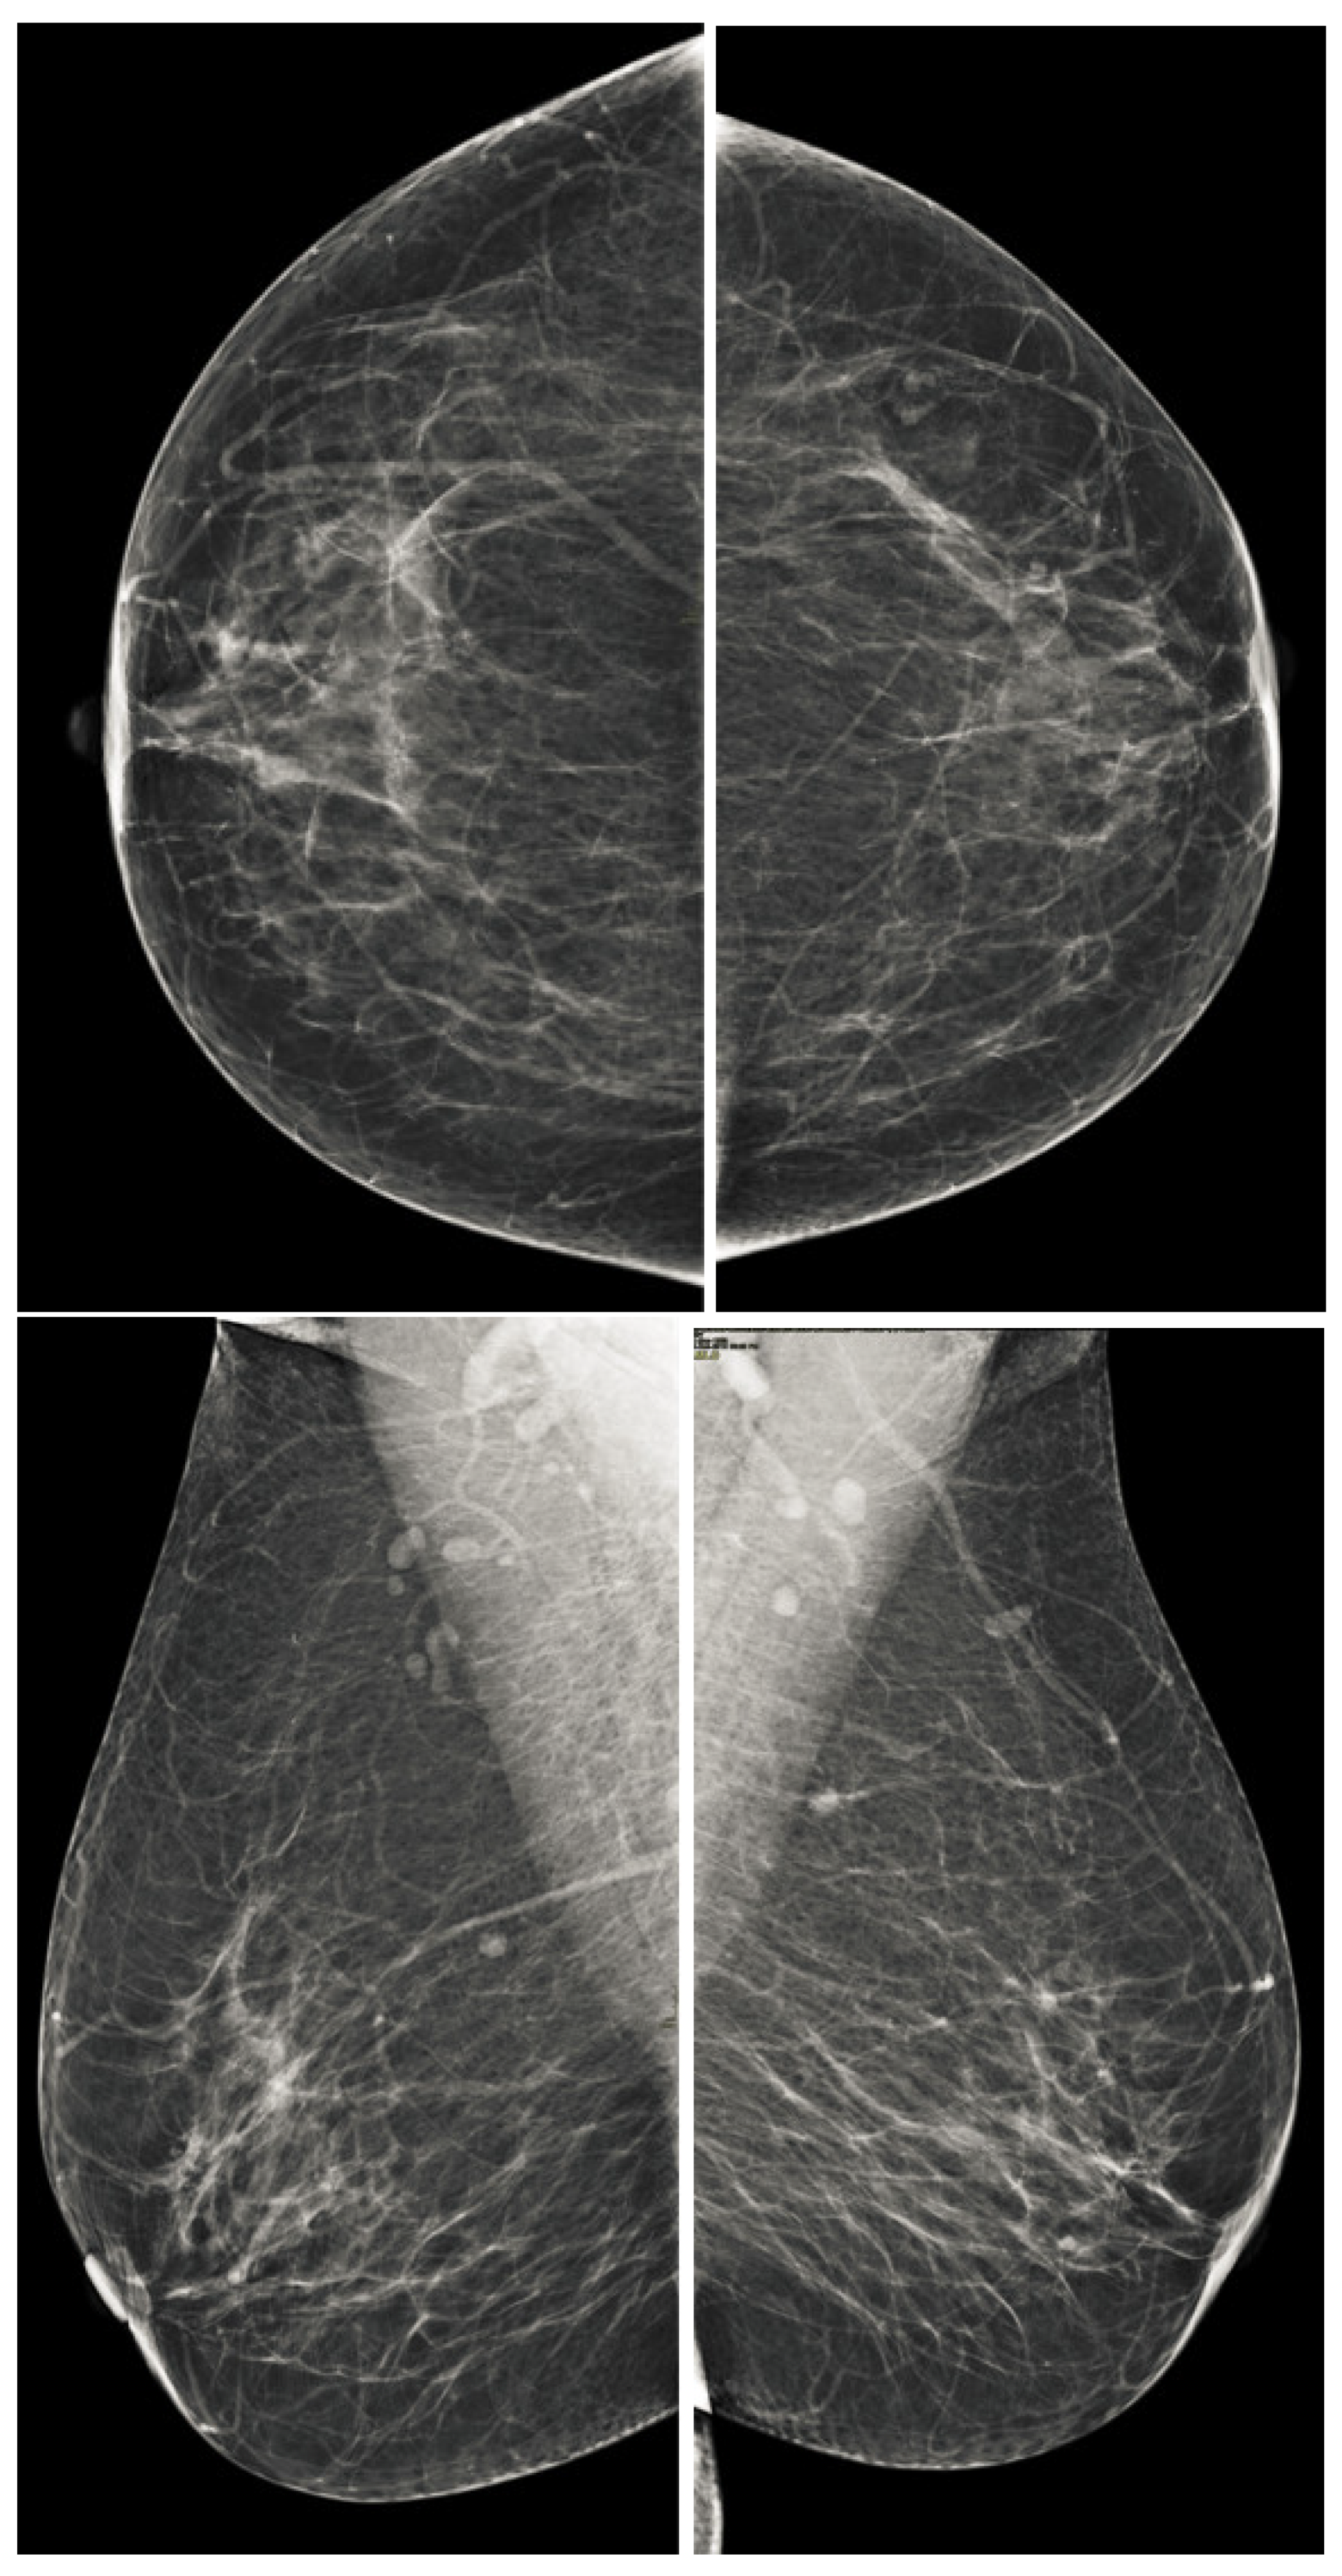

The implementation of any method depends on the nature of the data; it is necessary to analyze the databases before proposing a method of analysis for medical images. The mammographic images have analysed and found that there are two types of images: film screen mammographic images and digital mammographic images. The digital mammographic images are used for the proposed method. There were many challenges using digital mammographic images, and one of the most analyzed challenges was the detection and removal of pectoral muscles. The analysis of pectoral muscles depended on their geometric shape and their location in correspondence with their view [30,31]. There are two ways to view mammographic images, the carniocaudal (CC) view and the mediolateral oblique (MLO) view, and these views are shown in Figure 1. The pectoral muscle in the CC view is the semi-elliptical shape along the breast wall. The pectoral muscle in the MLO view is the shape in the upper mammogram coverage and roughly corresponds to the overlapping right-angled triangle shown in Figure 1. Both views have different issues and suffer from low contrast, but both contain the cancerous region in many cases. It is very important to remove the pectoral muscle from the breast region and classify the database of specific image views according to the BI-RADS classification as it facilitates the computerized process of detecting breast cancer.

Figure 1. Representation of standard mammographic views. The first rows represent the CC view of the right and left breast, and the second row represents the MLO view of the right and left breast.